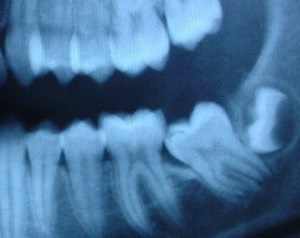

Toate caracteristicile structurii dinților acestui grup sunt reduse la rădăcinile lor. molarilor de minte - ea multiroot dinți (de la 2 sau mai multe). Adesea, ele sunt îmbinate cap la cap sau de legare

Uneori, în procesul de dezvoltare a fălcilor în începuturile unei dentiție sunt inversate. În acest caz, a opta tăiat printr-un rând nu este caracteristică dintelui localizare (aberant), care poate avea unul rădăcină.

Trebuie să spun că prezența rudimente molarilor de minte este încă nici o garanție că Grupul celor Opt în dentiția se încadrează în mod necesar în loc. Se întâmplă astfel încât chiar și un complet format molarii de minte pentru anumite motive, nu pot, eventual, să erupă și să rămână adânc în osul maxilarului. Acești dinți sunt numite afectate. și parțial erupt - poluretinirovannymi. Ele pot fi închise de către țesutul osos sau de gumă. Opt impactate, de regulă, ei au dimensiunea de obicei, și poate împinge „vecinii“ lor, afectate de carii și să provoace dezvoltarea dintilor sale adiacente, inflamate și rănit, așa că, la fel ca și restul dinților necesită o examinare atentă.